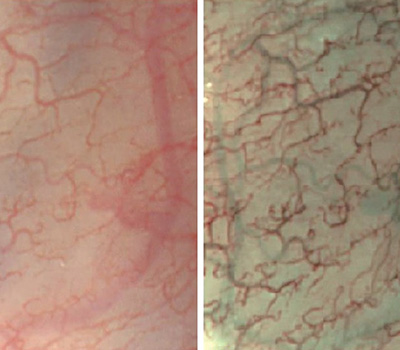

內(nèi)窺鏡有些時(shí)候使用白光做為光源,有些場合需要使用特定波長。應(yīng)用較多的有紫光415nm、綠光540nm、紅光600n,如圖所示,當(dāng)415nm紫光和600nm照射到器官組織時(shí),血管在在顯示器上有了更清晰的表現(xiàn)。